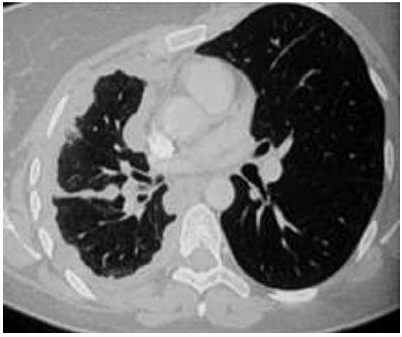

A imagem mostra um exame de tomografia de tórax que demonstra espessamento pleural > 1,0 cm, difuso, irregular e que se estende à pleural mediastinal, com envolvimento do plano cissural e com redução de volume do hemitórax comprometido.

O quadro é fortemente sugestivo de